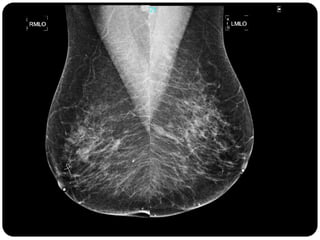

Paciente femenina de 66 años con historia clínica de 1er gesta antes de los 30 años y antecedentes de lactancia positiva, presenta una lesión palpable en la mama derecha. Los estudios radiológicos indican un diagnóstico de bi-rads 5, con biopsias revelando adenocarcinoma lobulillar infiltrante en la glándula mamaria derecha y adenocarcinoma ductal in situ en la izquierda. El caso fue evaluado por las doctoras Jacqueline Preciado Vargas y Beatriz E. González Ulloa.